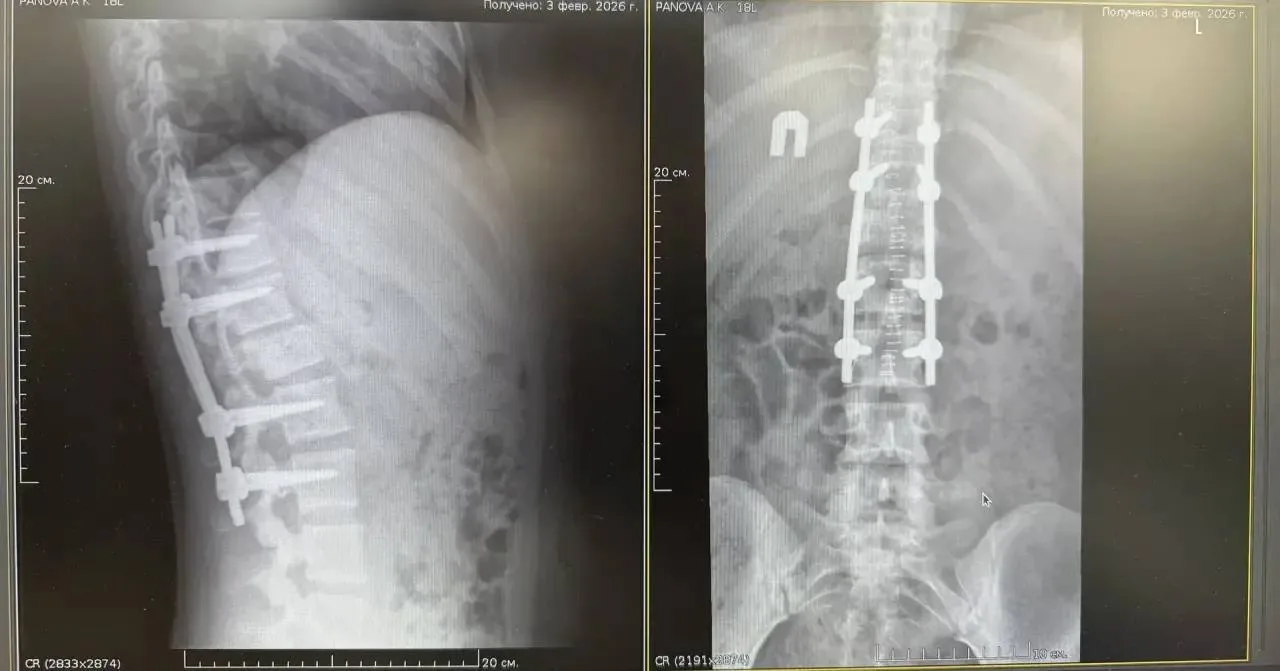

🥼Во Владивостоке нейрохирургии Тысячекоечной больницы вернули способность ходить 18-летней лыжнице с тяжёлой травмой позвоночника

19 января в эту больницу из Арсеньева была доставлена 18-летняя девушка с диагнозом «компрессионный перелом тела позвонка со стенозом позвоночного канала». Травма привела к сдавливанию спинного мозга, что вызвало парез ног и нарушение функций тазовых органов.

Дорога в стационар для этой пациентки выдалась тяжёлой: из-за дорожного инцидента машина скорой помощи резко затормозила, что вызвало у девушки с переломом позвоночника сильнейшую боль.

Нейрохирурги Тысячекоечной провели сложное 4-часовое вмешательство. В ходе операции врачи устранили компрессию нервных структур и стабилизировали позвоночник, установив металлоконструкцию. позволило не только дать спинному мозгу шанс на восстановление, но и полностью исключить риск повторного смещения позвонков.

Уже на вторые сутки после операции врачи начали ставить девушку на ноги, а на четвертые сутки она самостоятельно передвигалась по палате. Сейчас девушка выписана на амбулаторное лечение.